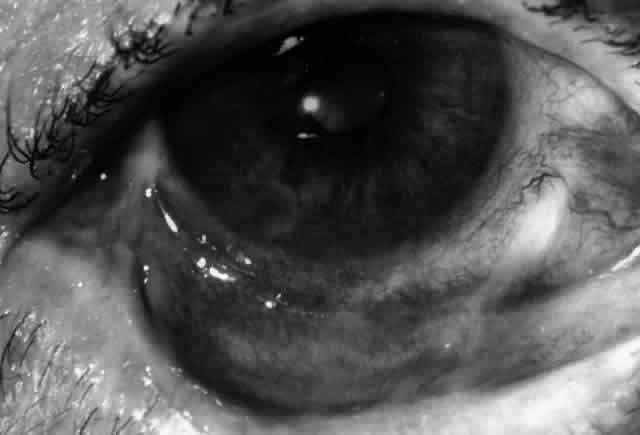

Clinically, the ocular disease in cicatricial pemphigoid (OCP) may present unilaterally in the form of a chronic, recurrent catarrhal conjunctivitis, but it eventually becomes bilateral. Subepithelial fibrosis is characteristic of stage 1 of OCP (Fig. 7). Stage 2 shows fornix foreshortening (Fig. 8), and symblepharon formation is the hallmark of stage 3 (Fig. 9). Stage 4, end-stage disease, is characterized by ankyloblepharon and surface keratinization (Fig. 10). Obstruction of the lacrimal ductules and meibomian gland ducts eventually produces an unstable tear film and progressive sicca syndrome, but it is to be emphasized that OCP is not a dry-eye syndrome until late in the disease course.20 Trichiasis and entropion occur because of the subepithelial fibrosis, with eventual keratopathy, corneal neovascularization, and corneal ulceration and scarring.20

Fig. 7. Stage 1 cicatricial pemphigoid, with cicatrizing conjunctivitis, and fine striae-type areas of subepithelial fibrosis, but without evidence of shrinkage of the conjunctiva.

Fig. 8. Stage 2 cicatricial pemphigoid, with fornix foreshortening and subepithelial fibrosis without frank symblepharon formation.

Fig. 9. Stage 3 of an eye affected by cicatricial pemphigoid. The conjunctival “shrinkage” continued and a frank symblepharon developed.

Fig. 10. Stage 4 cicatricial pemphigoid. Progressive shrinkage of the conjunctiva resulted in extreme trichiasis and distichiasis and keratopathy, with compromise of meibomian ductules and lacrimal ductules and the production of a totally dry eye.